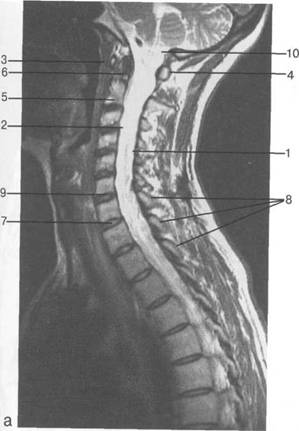

К моменту рождения (рис. 3.1) тело позвонка почти полностью состоит из к 141s183b 86;стной ткани, за исключением лимбусов, которые остаются хрящевыми. Дуга представлена двумя половинами, не слившимися ни с телом позвонка, ни между собой. Суставные отростки сохраняют перифе

MPT. Cw_v.